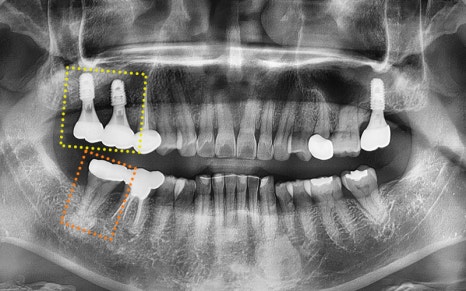

Seoul Of Dental Hospital always follows the principle of placing implants

parallel to the opposing teeth

and in a position where they occlude properly.

At the one-month check after placement,

we confirmed that there were no particular issues,

and decided to wait while the implant integrated well with the jawbone.

✅ Before > After

2024.11.22

▼ ▼ ▼

2025.04.15